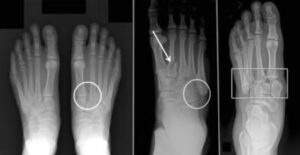

(Left) A subtle injury to the midfoot with widening between the first and second metatarsals (circle), compared with the normal foot on the left. (Center) A fracture of the second metatarsal (arrow) and a fracture of the cuboid (circle). (Right) A very severe injury of the foot from a high-energy event. It has resulted in a complete dislocation of the entire midfoot (box). Because no bones have been broken, a fusion may be recommended, given the high risk for future arthritis.